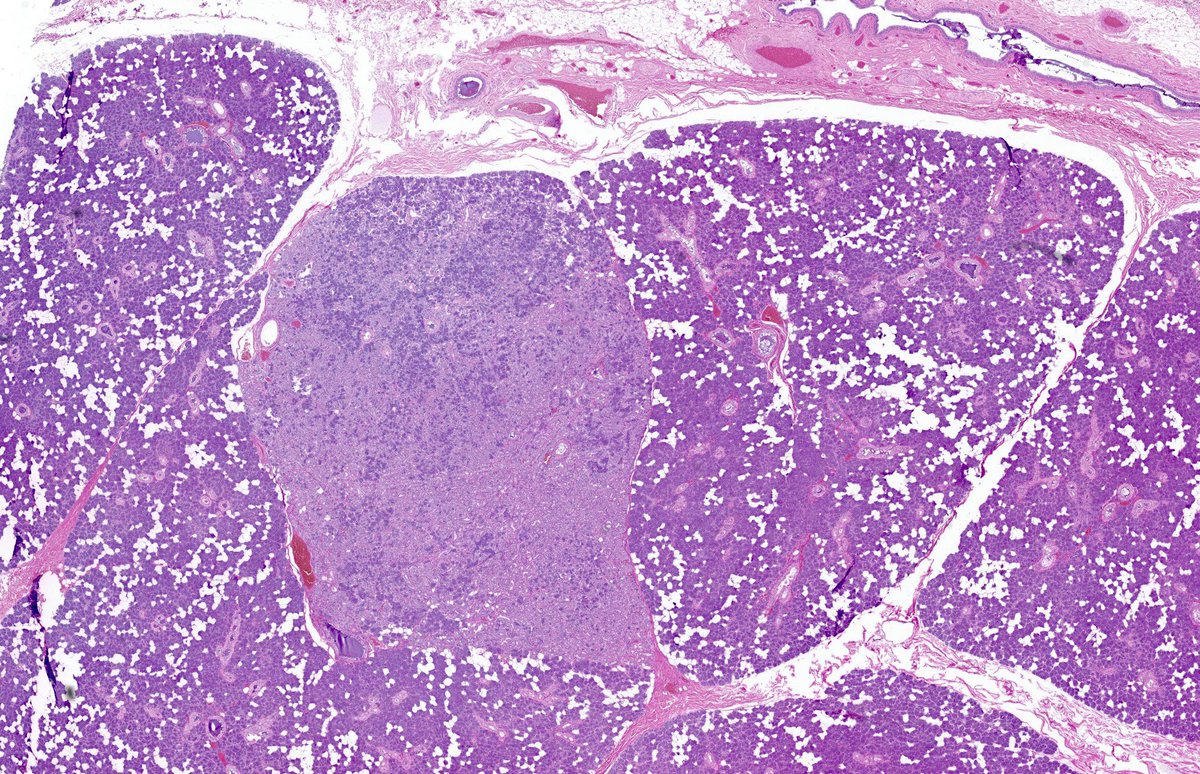

"BOW TIE". Papillary thyroid carcinoma. #FNA Thyroid. #Entpath #endopath #pathology #pathtwitter #PathTweetAward @MSWPathology @MyCytopathology @SamKhader

Head & Neck Pathology #ENTPath. Cytopathology, #FNApath